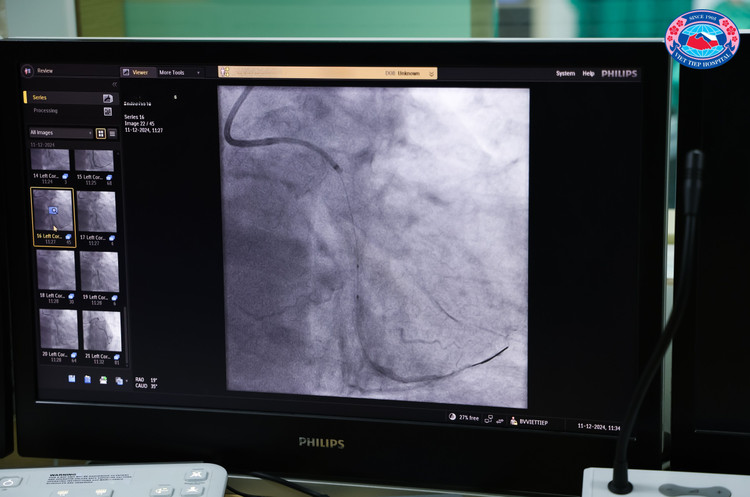

![]() |

| Tổn thương của bệnh nhân trên phim chụp - Ảnh BVCC |

Trước đó, người bệnh có tiền sử bệnh lý, như: Stent Động mạch vành phải (RCA12) (03/10/2024); Hẹp 90% Động mạch Mũ (LCx2); Hẹp 60% Động mạch Liên thất trước (LAD12); Tăng huyết áp, Đái tháo đường type 2 và rối loạn lipid máu.

Sau phần thảo luận lý thuyết, đoàn chuyên gia Nhật Bản đã phối hợp cùng ekip Khoa Can thiệp Tim và Mạch máu, Bệnh viện Hữu Nghị Việt Tiệp tiến hành thực hiện can thiệp trực tiếp cho một nam người bệnh 62 tuổi, cư trú tại quận Ngô Quyền, TP. Hải Phòng, được chỉ định can thiệp Động mạch mũ (LCx) còn hẹp 90% tổn thương rất phức tạp, mạch xoắn vặn, vôi hóa nhiều.